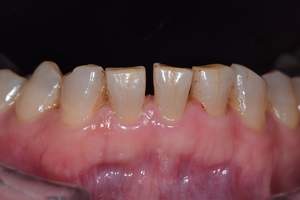

歯石除去

治療前

治療後

| 年齢 | 36歳・男性 |

| 主訴 | 歯石をとりたい |

| 治療内容 | 歯石除去 |

| 治療期間 | 30分 |

| 費用 | 約2,000円 |

| リスク・副作用 | ・歯ぐきの炎症が強いと歯石を取る際に出血することがあります。 ・処置後に歯がしみることがあります。 ・歯と歯の間に隙間ができるので、息が漏れ発音しにくいと感じることがあります。 ・歯ぐきの炎症が軽減すると歯ぐきが引き締まり、歯が長く見えることがあります。 |